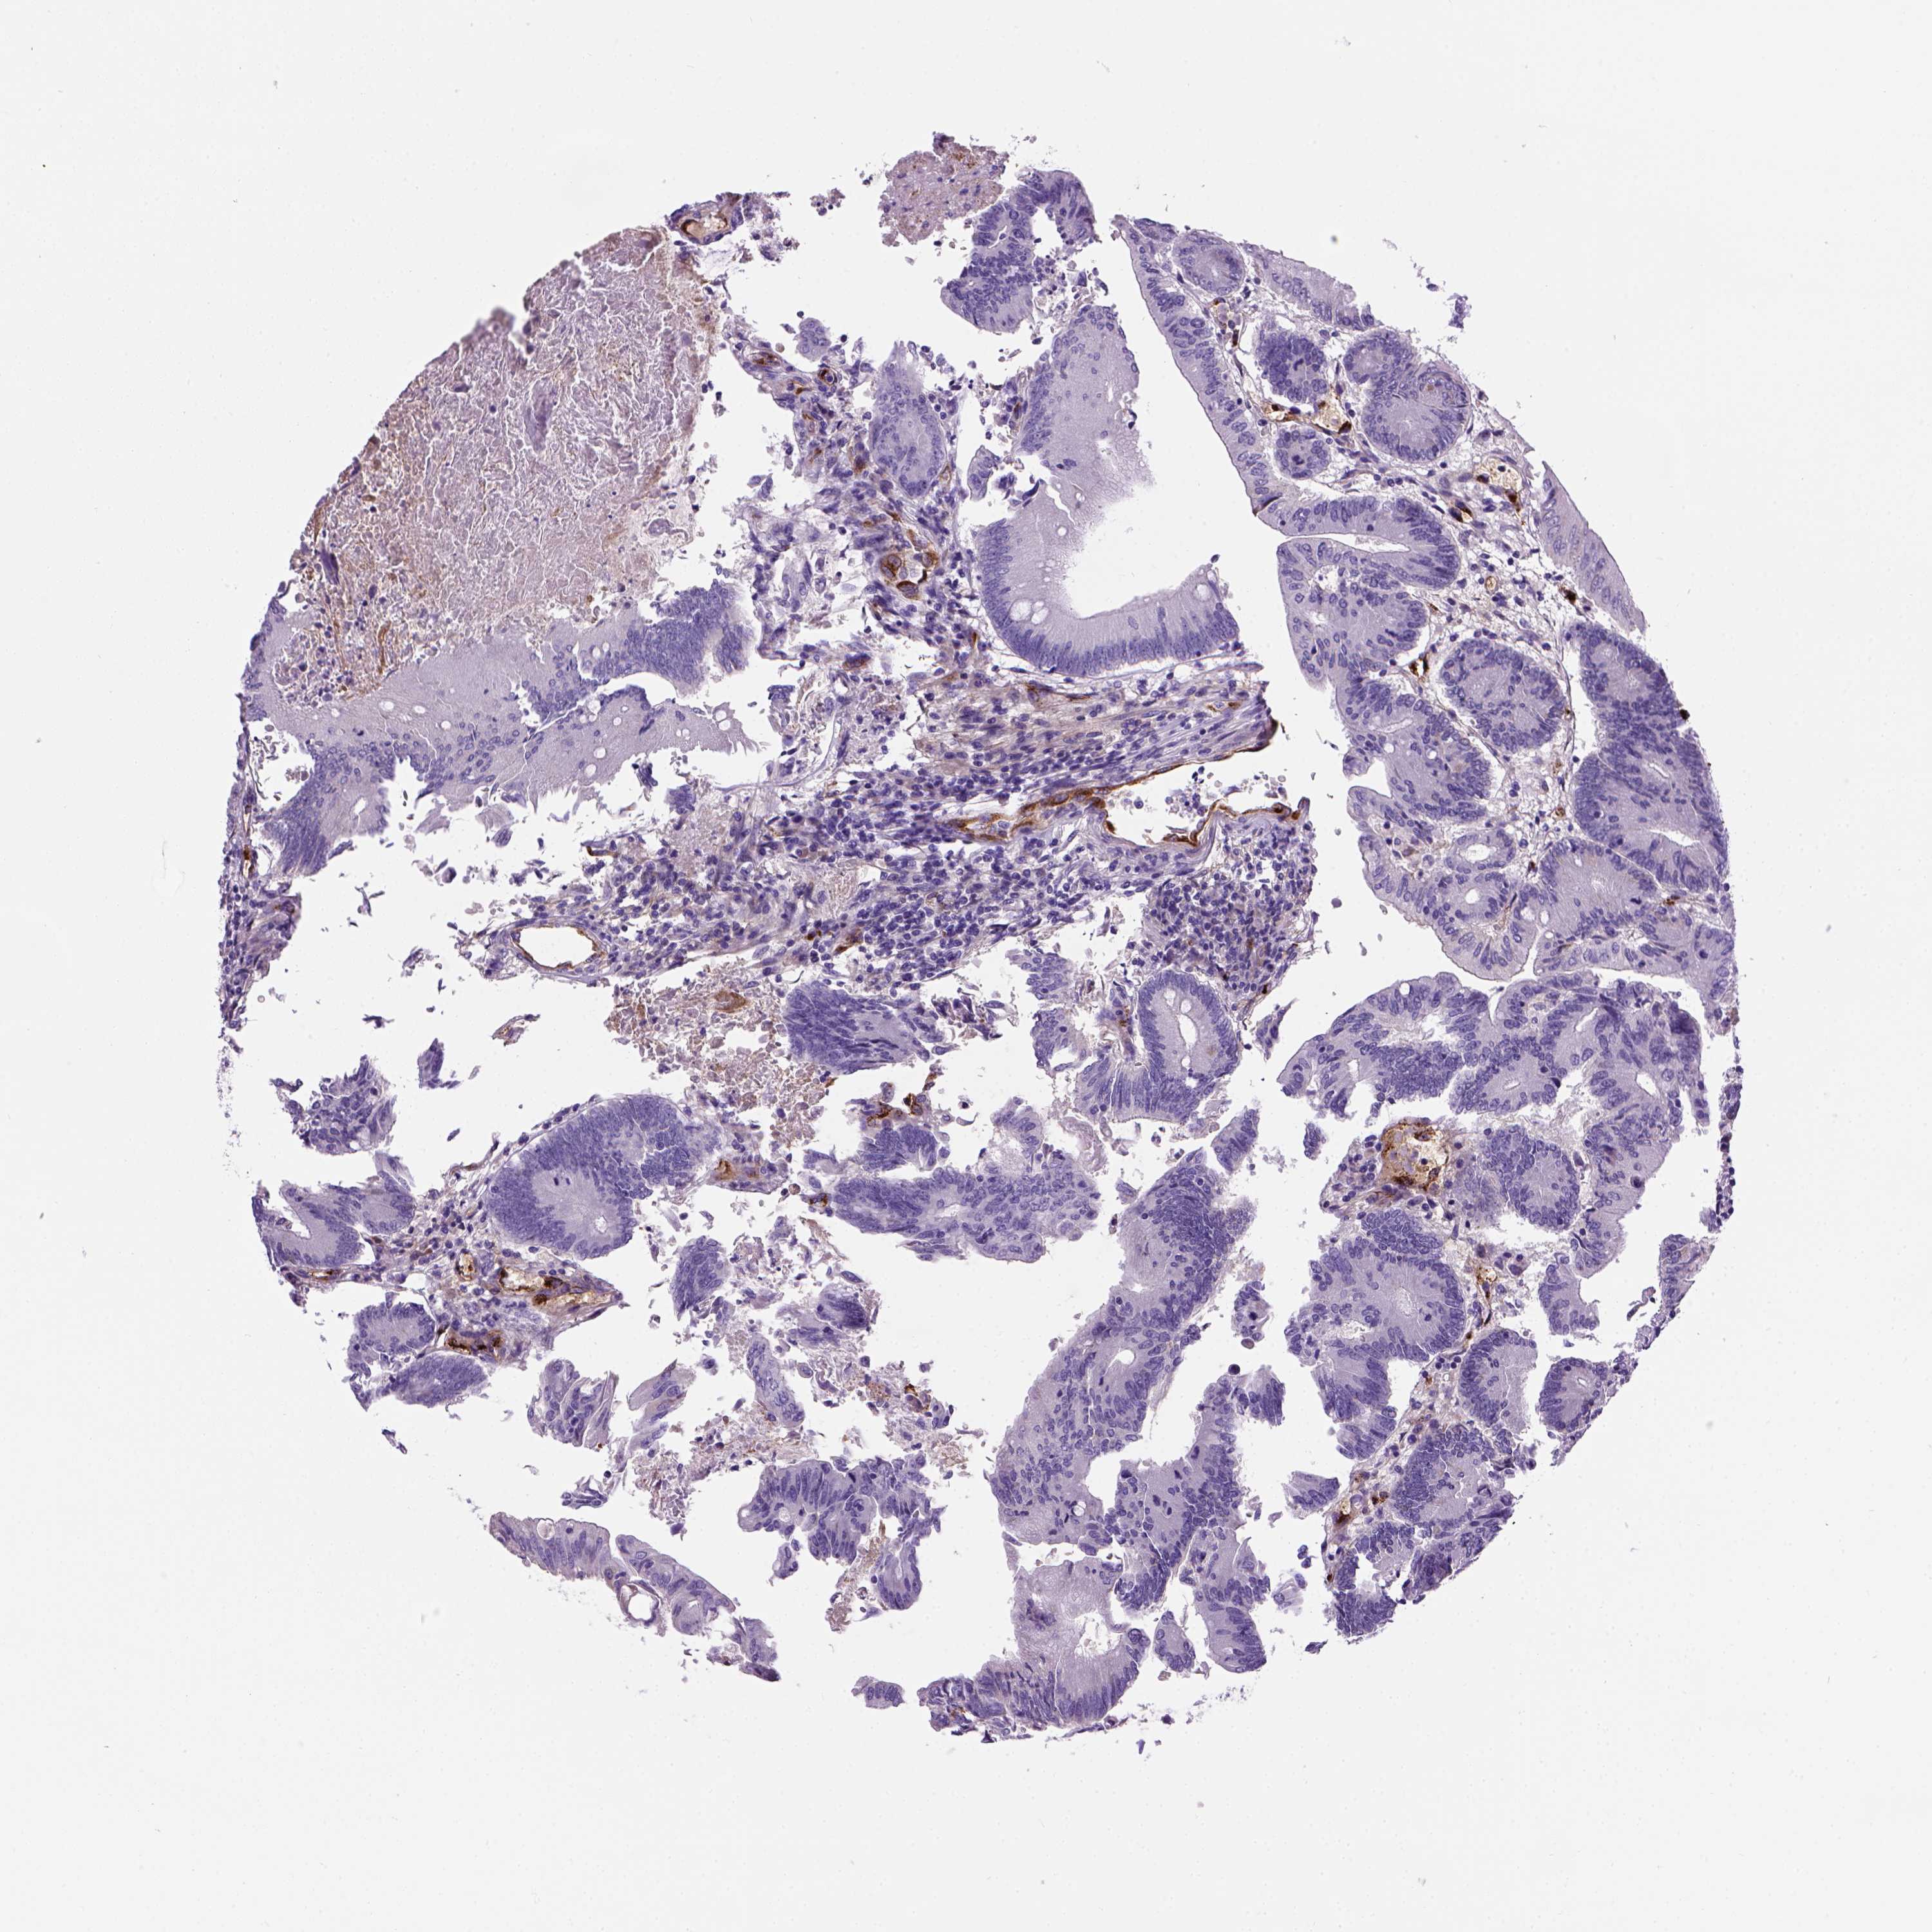

CANCER COLORECTAL CANCER Show tissue menu

COAD TCGA COAD VALIDATION READ TCGA READ VALIDATION PROTEIN COAD CPTAC PROTEIN EXPRESSION

ANTIBODIES

AND

VALIDATION